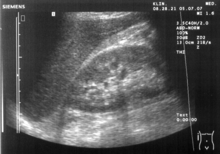

Ultrasound of liver (left side of the image) and right kidney (right side of the image) and Morison's pouch, not containing fluid.- Abdominal CT, showing Morison's pouch as the dark margin surrounding the right kidney (at lower left corner of image).